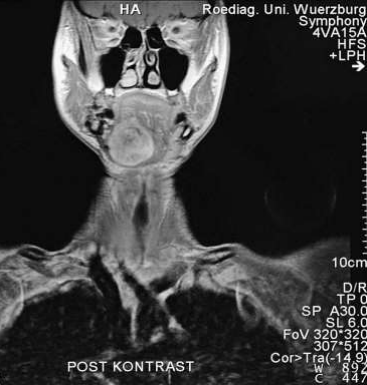

Fig 6: März 1998: reconstruction of the lower jaw with vascular stalked fibula from left side

Figure 6